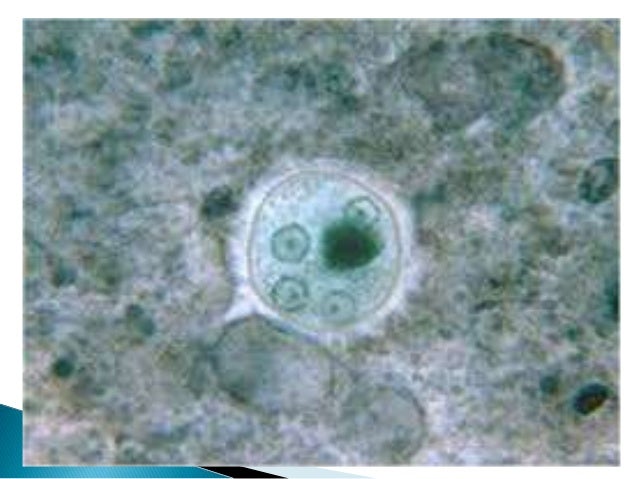

El parasito es adquirido mediante agua y alimentos contaminados, donde se aloja en forma quística, ya que es estadio mas resistente al acido que presenta el estómago. Una vez alojado en el intestino se rompe la capa de quitina y tras un desenquistamiento libera cuatro o cinco células alojadas en su interior para luego multiplicarse y desarrollar en el estadio infectivo llamado trofozoíto que se alimenta de bacterias intestinales, fagocita eritrocitos y del bolo alimenticio. Su diámetro es entre 15 y 60 micrones, y presenta un protoplasma que se divide en un ectoplasma  y endoplasma.